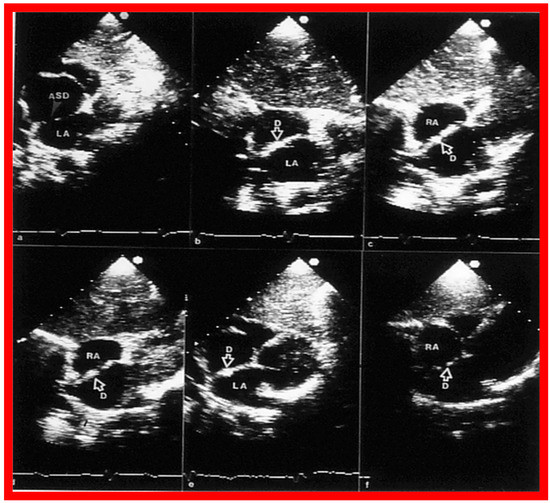

2. Diagnosis

- Singh, G.K.; Marino, C.; Rao, P.S. Ultrasound as an adjunct to cardiac intervention in the pediatric patient. J. Invasive Cardiol. 1996, 8, 341–349. [Google Scholar] [PubMed]